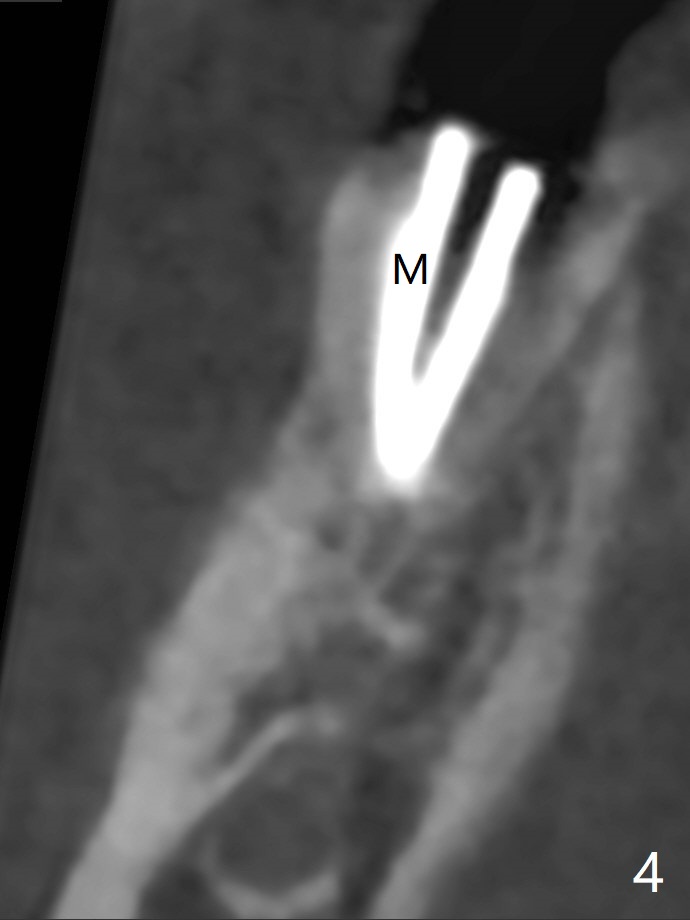

The tooth #30 of a 47-year-old woman has lower buccal crest (Fig.1-3 ^). To prevent post-extraction buccal plate collapse, closed socket shield (Fig.6,8-10 *) will be conducted in the mesial (Fig.1,4-6) and distal (Fig.2,7-10) roots. To decrease vibration, the buccal edge of the roots will be trimmed first (Fig.5,6 a) before root section (Fig.6 b).